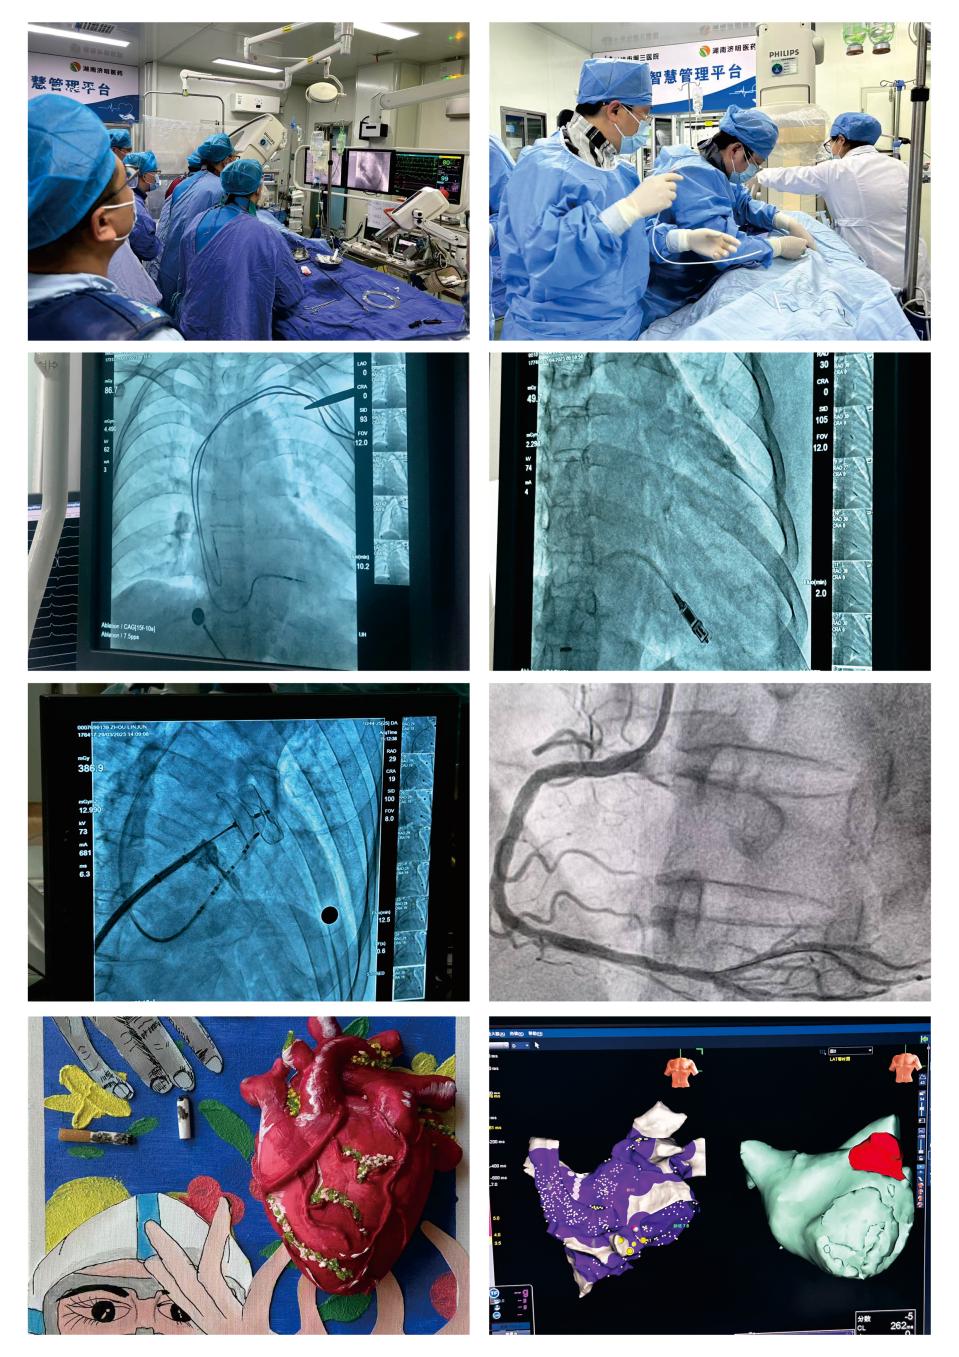

长沙市心力衰竭诊疗技术创新中心

依托长沙市第三医院心血管病学科创建,负责人为心血管内科四病室主任肖晓霞。心血管病学科是省级省临床重点专科建设项目、长沙市临床重点培育学科、中国心衰中心湖南省首批认证单位、国家心衰医联体成员单位科室、国家标准化心血管与代谢疾病中心示范中心、国家标准化胸痛中心示范中心、国家标准化心力衰竭中心示范中心、长沙市血管病防治研究所建设单位等,在冠心病介入治疗、CTO病变介入治疗、血管内超声、旋磨、IABP、临时和永久起搏器的植入、CRTICD、先天性心脏病的封堵、房颤及其他快速心律失常的射频消融诊断治疗等方面经验丰富。

长沙市心力衰竭诊疗技术创新中心以多学科诊疗团队临床实践为核心,致力于解决心力衰竭诊疗难题。中心将构建多学科诊疗体系,形成规范化、层次化的心衰治疗闭环,凭借团队优势定制个性化方案;建立临床科研攻关机制,搭建数据库进行数据分析,结合临床与基础研究,为防治提供新方案;倡导心衰患者运动康复治疗,改善症状、降低住院风险;同时建设区域化、立体化的心衰救治网络,打造连接多地医疗机构的联盟。